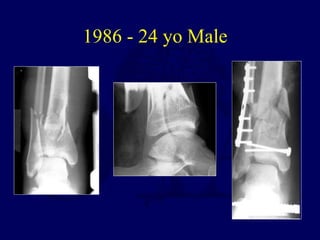

1986 - 24 yo Male

1 year

7 years

14 years

 Works light labor

 Prefers high top boots

 Occasional pain

 Ankle score 80